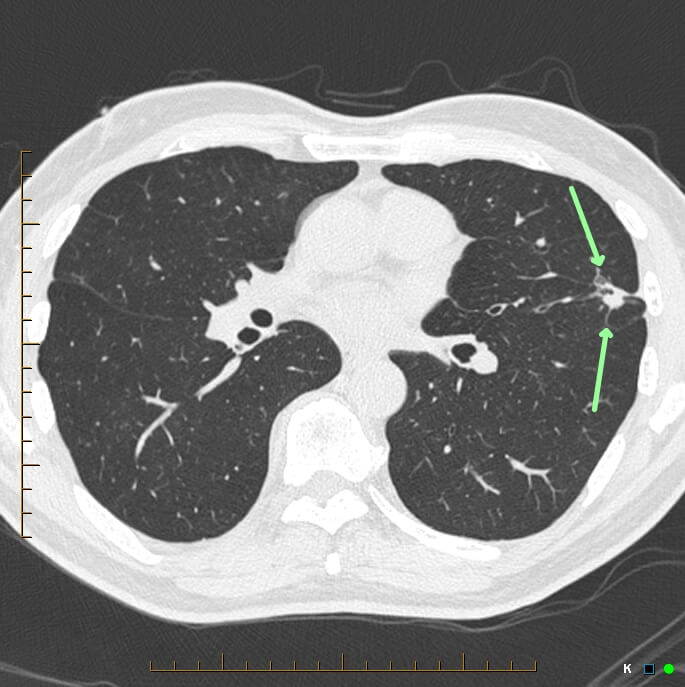

Low Dose CT lung screening is a non-invasive scan that lasts for a relatively short time. The scan itself is done in seconds and no injection is required.

Prior to the scan, a CT radiographer will explain the procedure to you and get you changed into a gown. Patients place their arms back over their head, lie comfortably on the CT examination table and are required to follow breathing instructions for the scan. The total time for the preparation and scan time is usually only 10-15 minutes. Once the scan is completed you will be able to return to normal activities.